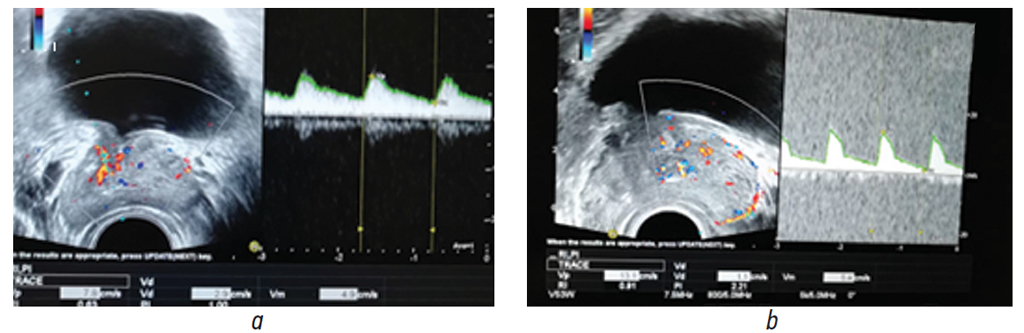

Исходно у пациентов обеих групп было выявлено ухудшение кровотока в предстательной железе, что проявлялось снижением значений основных доплерометрических показателей (рис. 1).

Рис. 1. Пациент П. (основная группа). Трансректальное ультразвуковое исследование простаты в доплеровском режиме до лечения: а — уретральные ветви артерии простаты; b — капсулярные ветви артерии простаты

Fig. 1. Patient P. (main group). Doppler TRUS of the prostate before treatment: a – urethral branches of the artery of the prostate; b – capsular branches of the prostate artery